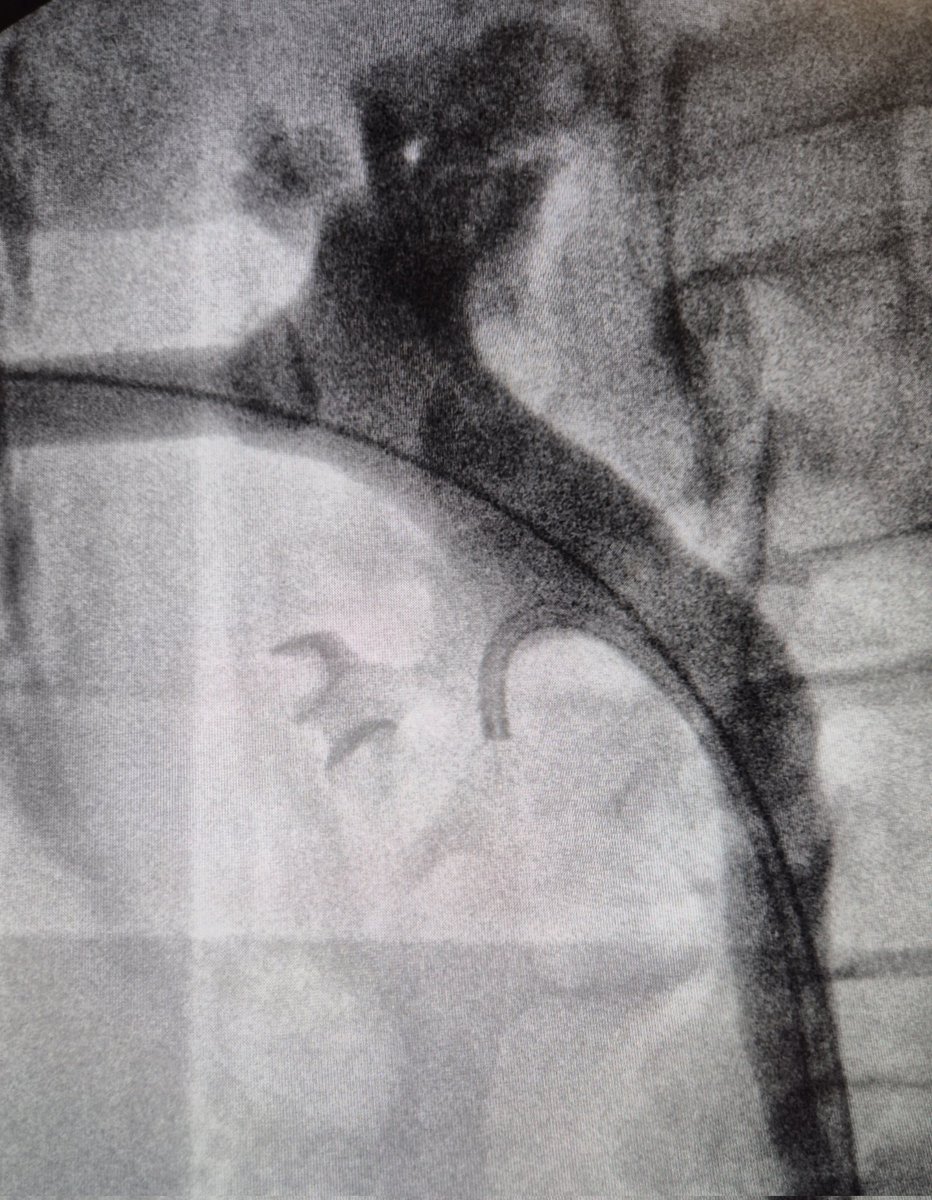

Always a pleasure to be back in Barcelona #UROFORUM hosted by @AntonioAlcarazA & @UroDrLopez @UniBarcelona for a nice live demonstration of a 30min #miniperc supplied by @OlympusUrology & @ClearpetraL ® aspirating sheath: bottom line? There is still room for #PCNL! Many thanks to all local team for the support!